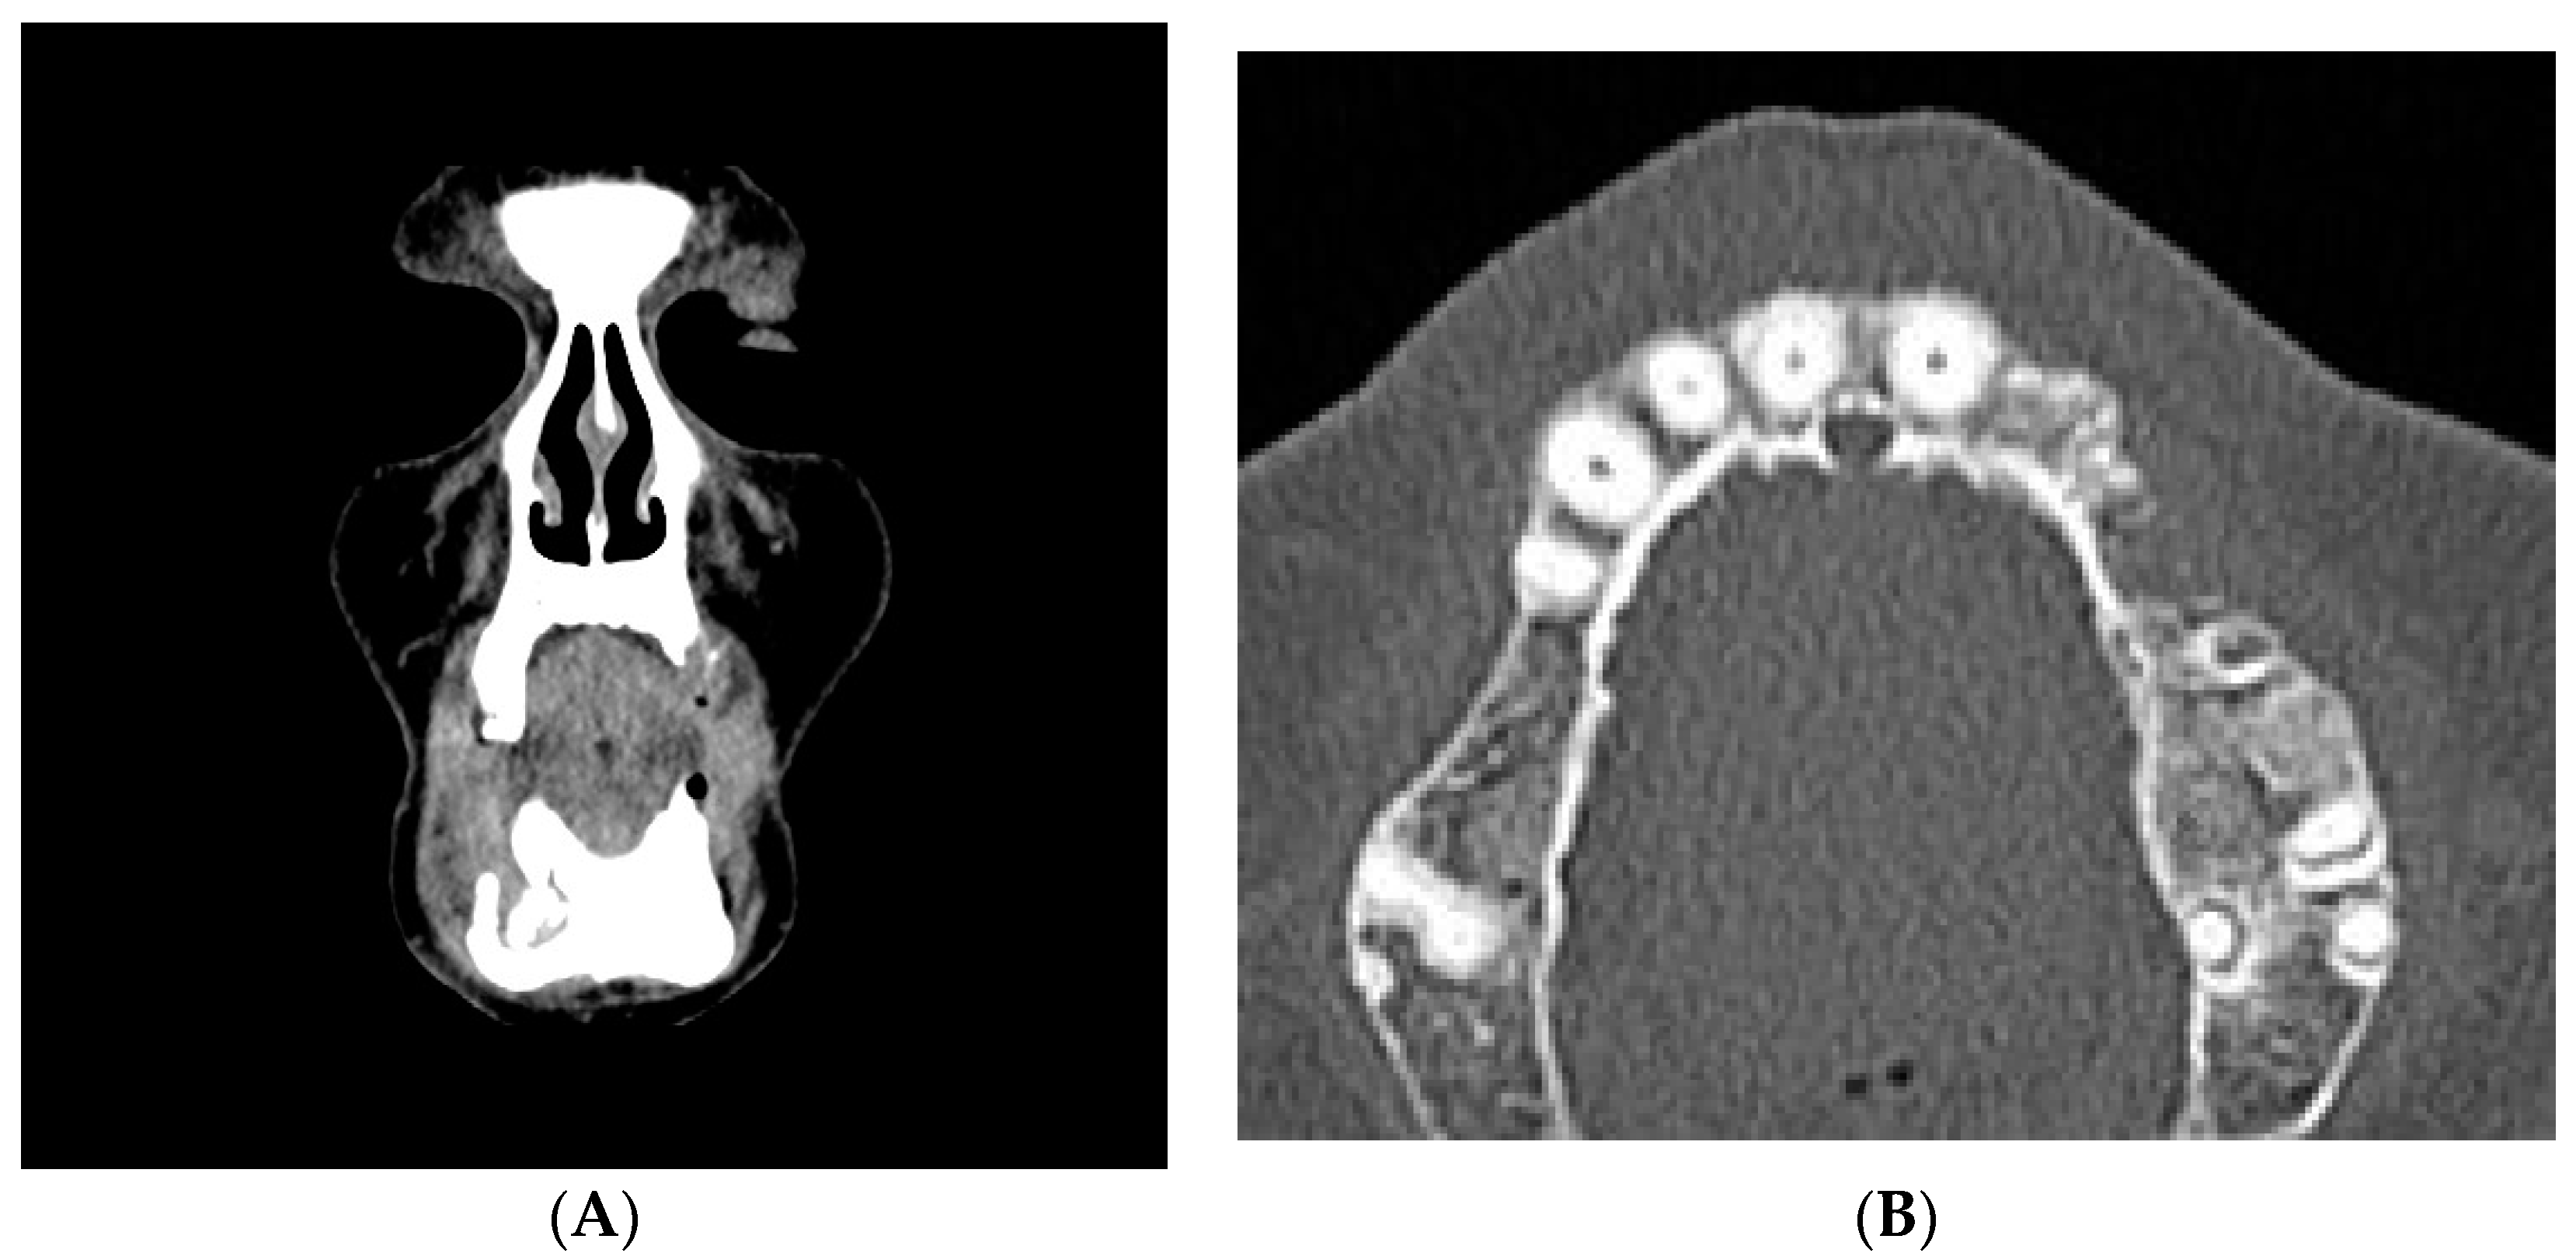

2. Case Report

- Bedogni, A.; Fedele, S.; Bedogni, G.; Scoletta, M.; Favia, G.; Colella, G.; Agrillo, A.; Bettini, G.; Di Fede, O.; Oteri, G.; et al. Staging of osteonecrosis of the jaw requires computed tomography for accurate definition of the extent of bony disease. Br. J. Oral Maxillofac. Surg. 2014, 52, 603–608. [Google Scholar] [CrossRef] [PubMed]

- Wilde, F.; Heufelder, M.; Lorenz, K.; Liese, S.; Liese, J.; Helmrich, J.; Schramm, A.; Hemprich, A.; Hirsch, E.; Winter, K. Prevalence of cone beam computed tomography imaging findings according to the clinical stage of bisphosphonate-related osteonecrosis of the jaw. Oral Surg. Oral Med. Oral Pathol. Oral Radiol. 2012, 114, 804–811. [Google Scholar] [CrossRef] [PubMed]